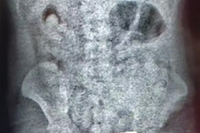

Nas redes sociais, Naíny publicou um vídeo onde descreve o estado da prima e os desafios enfrentados após o ataque. A mulher já passou pela primeira cirurgia de cirurgia facial, mas ainda precisa de novos procedimentos, incluindo um enxerto de pele e a colocação de tecido no queixo, devido à profundidade minúscula por uma das mordidas.

image Arquivo pessoal

"Ela está bem, na medida do possível, e está se recuperando, mas fica o trauma psicológico e o rosto dela, que, apesar da cirurgia de reconstituição, não está do mesmo jeito que era antes. Perdeu o formato de antes", lamenta Naíny. De acordo com a prima, a vítima também não fala ainda devido às fortes dores que sente.